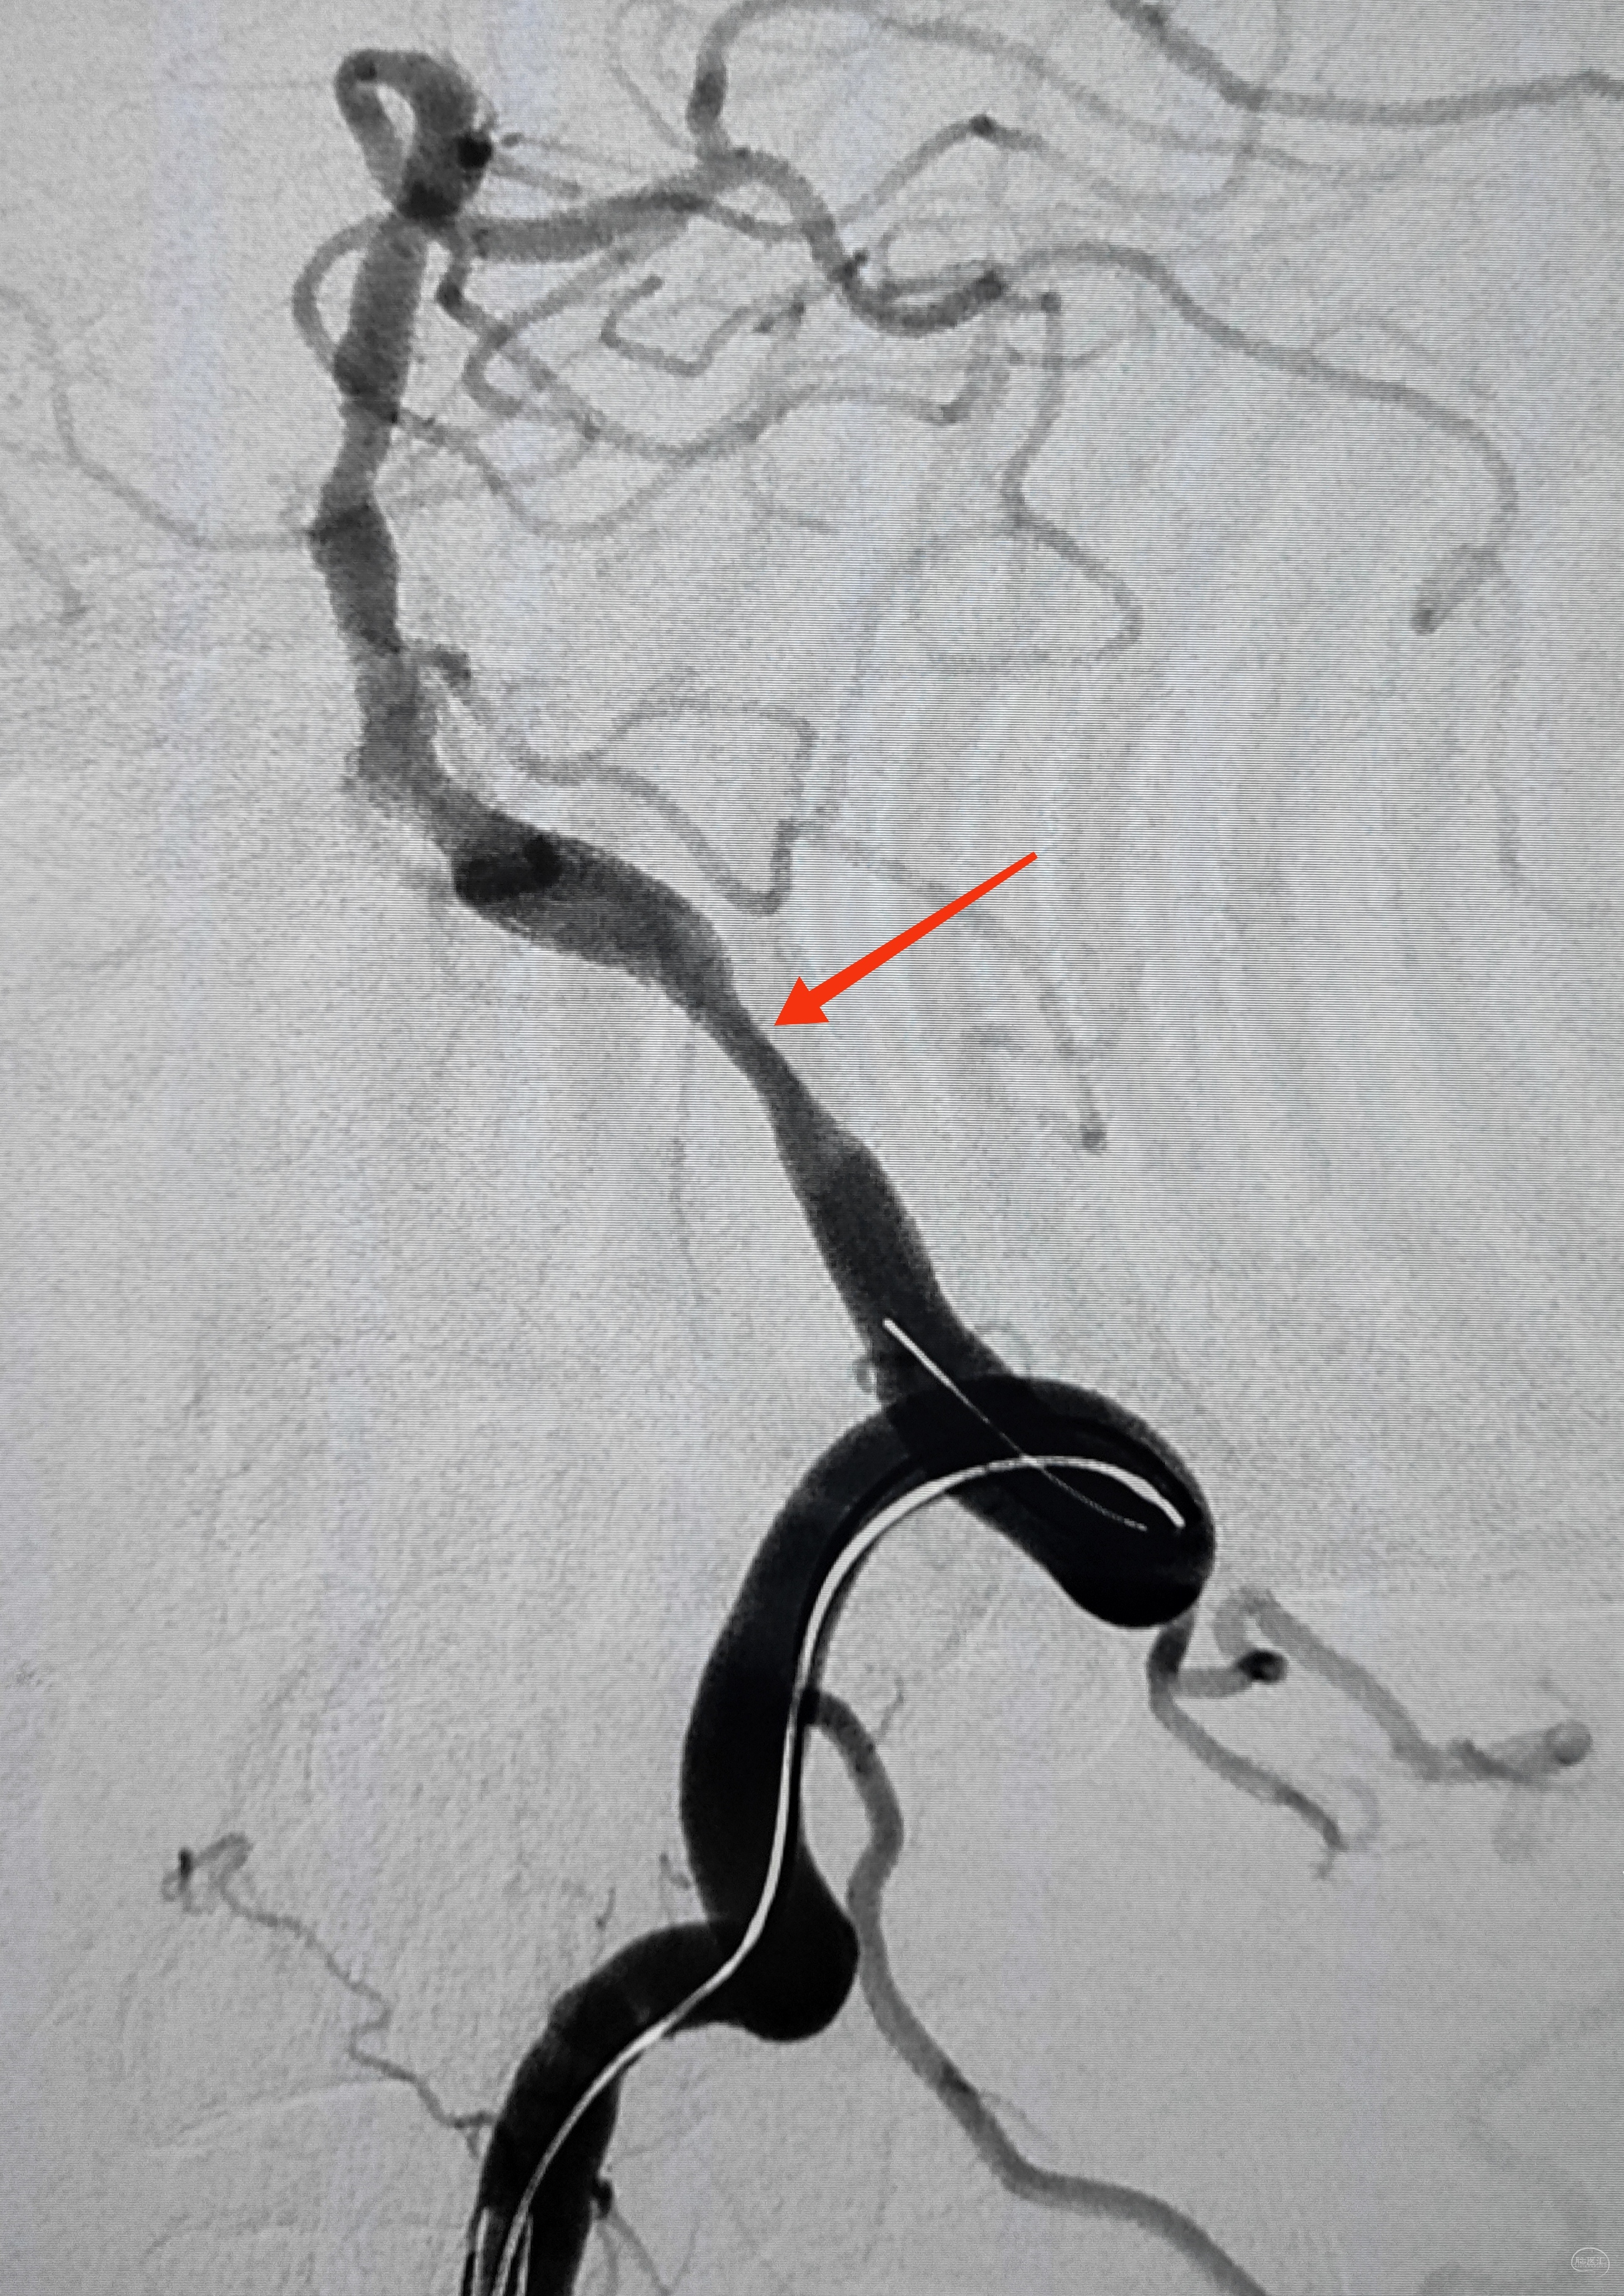

如约初诊:女儿彬彬有礼,父亲中年男性,52y,间断头晕不适多年,口服药物效果不佳,遂在外院做了脑血管造影,推荐过来做脑血管搭桥。调取DSA影像后感觉血管比口述的情况复杂,远不是搭桥能够解决问题,毕竟是“头晕”为主诉,下面结合图像,分述如下:

弓上造影初见:问题(一)左侧锁骨下动脉闭塞,主诉为头晕,双上肢收缩压差>20mmHg,这就是祸根?接着看弓上造影晚期像。

弓上造影晚期:剂量因素,逆流盗血隐隐可见,复合预期,那就看看对侧椎动脉情况吧